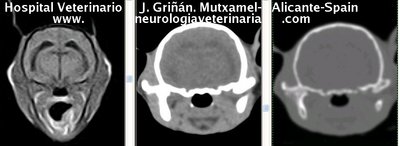

Se muestran cortes transversales de Resonancia Magnética (imagen a la izqda del lector), TC contrastado para tejidos blandos (imagen del centro) y TC contrastado para tejidos duros (imagen de la derecha del lector).

Nótese como la Resonancia supera al TC en el contraste de tejidos blandos (encéfalo y médula espinal) y en el de líquidos (ojo y líquido cefalorraquídeo), mientras que el TC supera a la resonancia en el contraste de tejidos duros (hueso) y aire (senos, cavidad nasal y bullas)

Cortes a nivel de los bulbos olfatorios